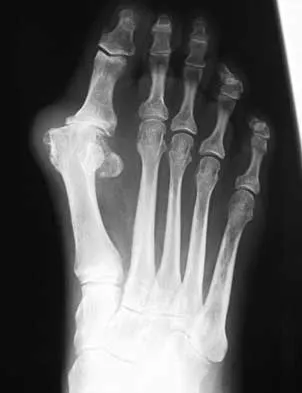

Question 77High Yield

A 61-year-old woman has increasing pain in her left great toe. She states that she has had discomfort for years but now has pain with all shoe wear. A radiograph is shown in Figure 35. To provide the most predictable pain-free result, treatment should consist of

Orthopedic Surgery Board Review 2026 | High-Yield MCQs - Set 1 - Figure 58

Explanation

Because the patient has a hallux valgus with increased intermetatarsal and hallux valgus angles and advanced degenerative arthritis of the joint, arthrodesis of the first metatarsophalangeal joint will provide the most predictable pain-free result. An attempt to correct the bunion with a bunionectomy or osteotomy would most likely fail. The hallux valgus and advanced degenerative changes put the foot beyond the indications for a cheilectomy. Long-term results with silicone arthroplasty have been disappointing. Mann RA: Disorders of the first metatarsophalangeal joint. J Am Acad Orthop Surg 1995;3:34-43.